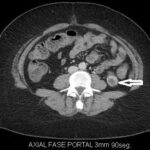

Fase nefrográfica o portal

Se logra a partir de los 80 a 180 segundos posteriores a la inyección del contraste; el medio de contraste se encuentra en los túbulos colectores y asa de Henle durante esta fase y su utilidad se basa en el aumento homogéneo del parénquima renal, lo que permite una mejor delimitación de la masa renal.

Durante esta fase se presenta el mayor realce de los tumores sólidos, por lo que se logra una mejor caracterización de las masas indeterminadas. En un estudio sobre la caracterización de las masas renales menores a 3 cm se concluyó que durante las exploraciones en fase nefrográfica se permitió una mayor detección de lesiones y una mejor caracterización de las masas renales pequeñas que en las exploraciones de fase corticomedular 3-5 (Fig. 3).